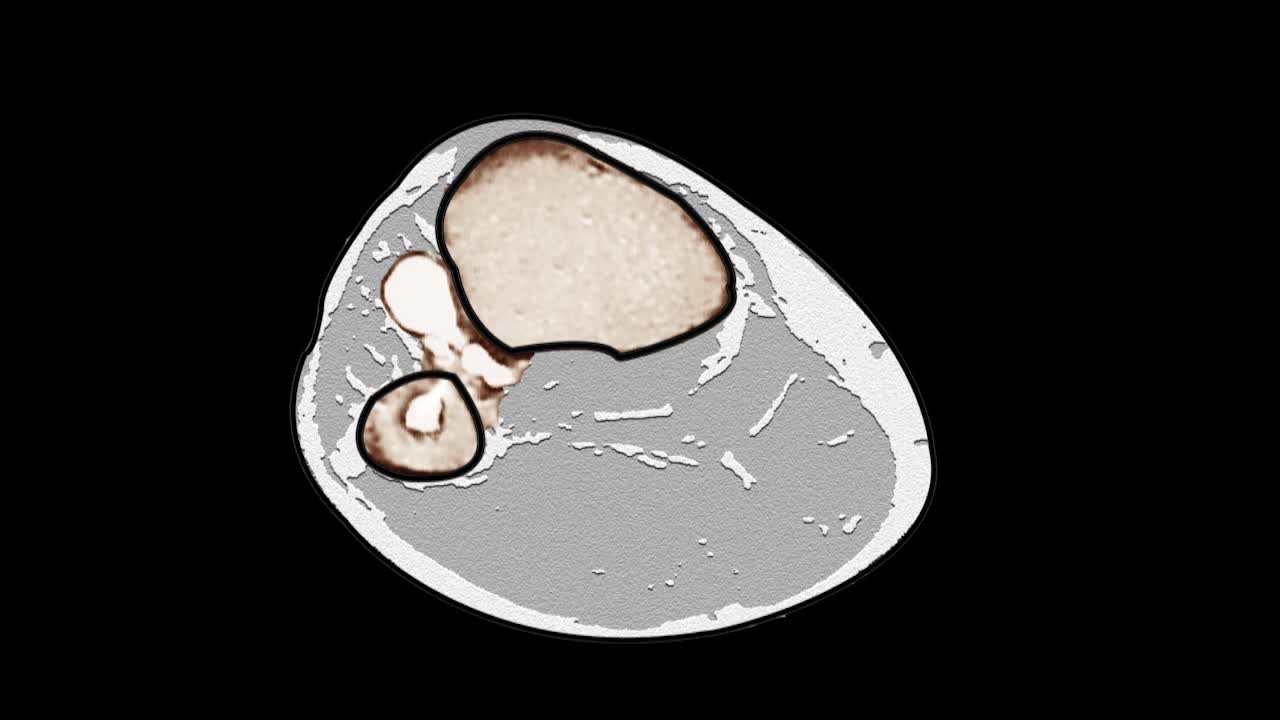

Reliability and Function fromACSetting IE Component Rotation Parallel to the Sagittal Kinematic Plane in TKA 医学讲坛 2022年07月15日 67 点赞 0 评论 213 浏览